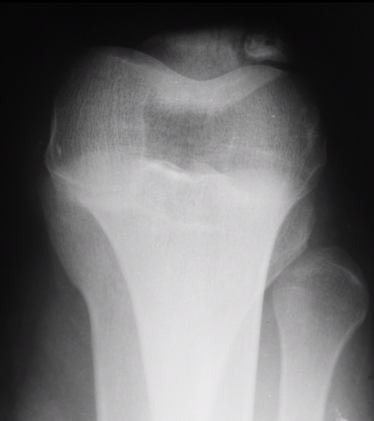

This is a subtle bipartite patella with lateral abnormality

Case courtesy of Dr. Sumit Verma, Radiopaedia.org. From the case rID: 74103

Case courtesy of Dr. Aditya Shetty, Radiopaedia.org. From the case rID: 27156